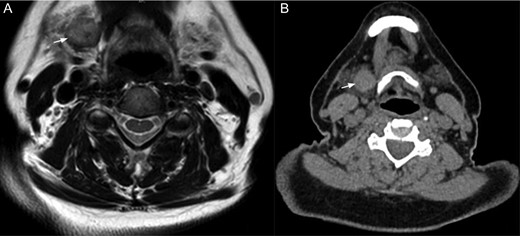

The staging exams (Fig. 1) revealed multiple solid heterogeneous isointense lesions on the left kidney, consistent with multicentric RCCC. Greater omentum and left suprarenal gland nodules were also described. With the previous findings, the patient underwent systemic treatment with pazopanib (a tyrosine kinase inhibitor) for 12 months, showing a poor oncologic response. A surgical approach was decided.

The white arrow shows the right submandibular gland in (A) magnetic resonance in T1 and (B) CT scan.